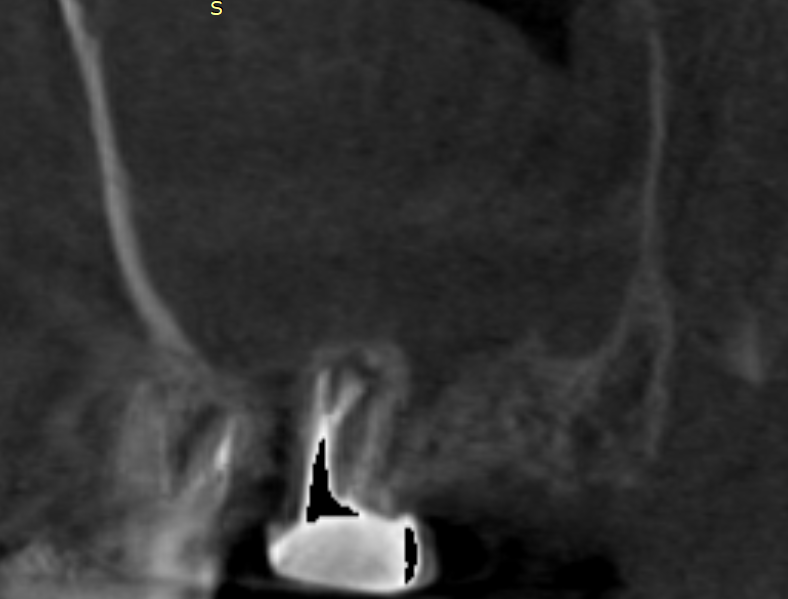

Добрый вечер. История очень длинная...  пол года болею именно клинически, хотя процесс как оказалось с 2020 года где то, тогда когда чувствовал себя здоров полностью, из-за причинных зубов.

26 зуб в марте я попросил что бы попробовали перелечить. нашли в итоге 4 канал и спустя несколько месяцев отмечается улучшение небольшой, обрастает костью, 8 удалил 1 апреля,  3 недели назад перепаковали 7, там перфорация была., долго ждал специалиста по эндодонтии, ибо для остальных даже эндодонтов он труп был, но опять же прогноз под вопросом и я это понимаю, переделал каналы и закрыл перфорацию врач известный на весь снг, фамилии писать не буду, далее было 2 гайморотомии, одна через нос, после уже экстраназальная, при второй лишь удалось вытащить мицетому с пломбировочным материалом. На 7зуб на сл  неделе попробуем временную коронку... После операции второй прошло 10 дней, но клиника вот вся эта полугодичная еще сохраняется.

Скажите, есть ли шанс попробовать подождать еще, касательно 6 и 7 зуба, или как быть ?

image.png.12405cfc51414f93b6b5a12ce7098a18.pngimage.png.f7a79906207cc5c9c8bcd95d65b7bb29.png